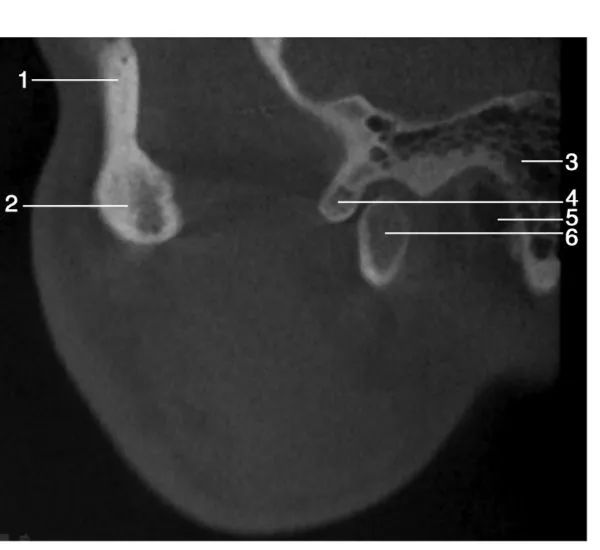

1.眶外缘( lateral pole of orbit) ; 2.颧骨( zygoma) ; 3.乳突气房( mastoid cells) ; 4.关节结节( articular eminence of temporal bone) ; 5.外耳道( external acoustic meatus) ; 6.髁突( mandibular condyle)